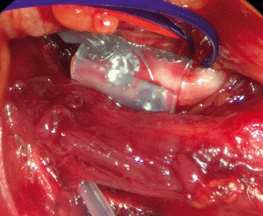

Intraoperativ wird die Cuff-Elektrode um den Hauptstamm des Nervus hypoglossus geschlungen. Intraoperativ wird die Cuff-Elektrode um den Hauptstamm des Nervus hypoglossus geschlungen. © Verse T, Wiest G. Hamburger Ärzteblatt 2021; 75: 12-16 © Hamburger Ärzteverlag, Hamburg